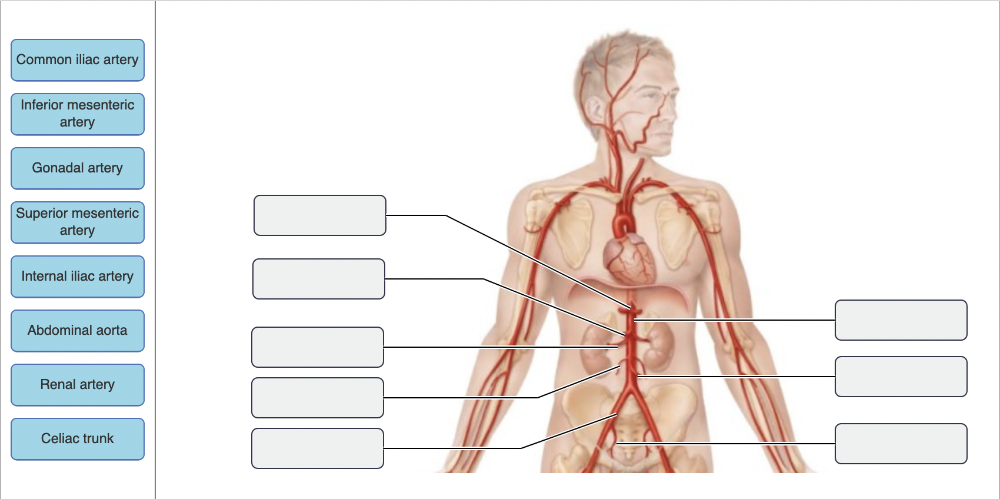

The branches of the abdominal aorta include all of the following except:

- superior mesenteric

- celiac trunk

- gonadal

- bronchial

bronchial

Drag the appropriate labels to their respective targets.

Drag the appropriate labels to their respective targets.

Drag the appropriate labels to their respective targets.

Drag the appropriate labels to their respective targets.